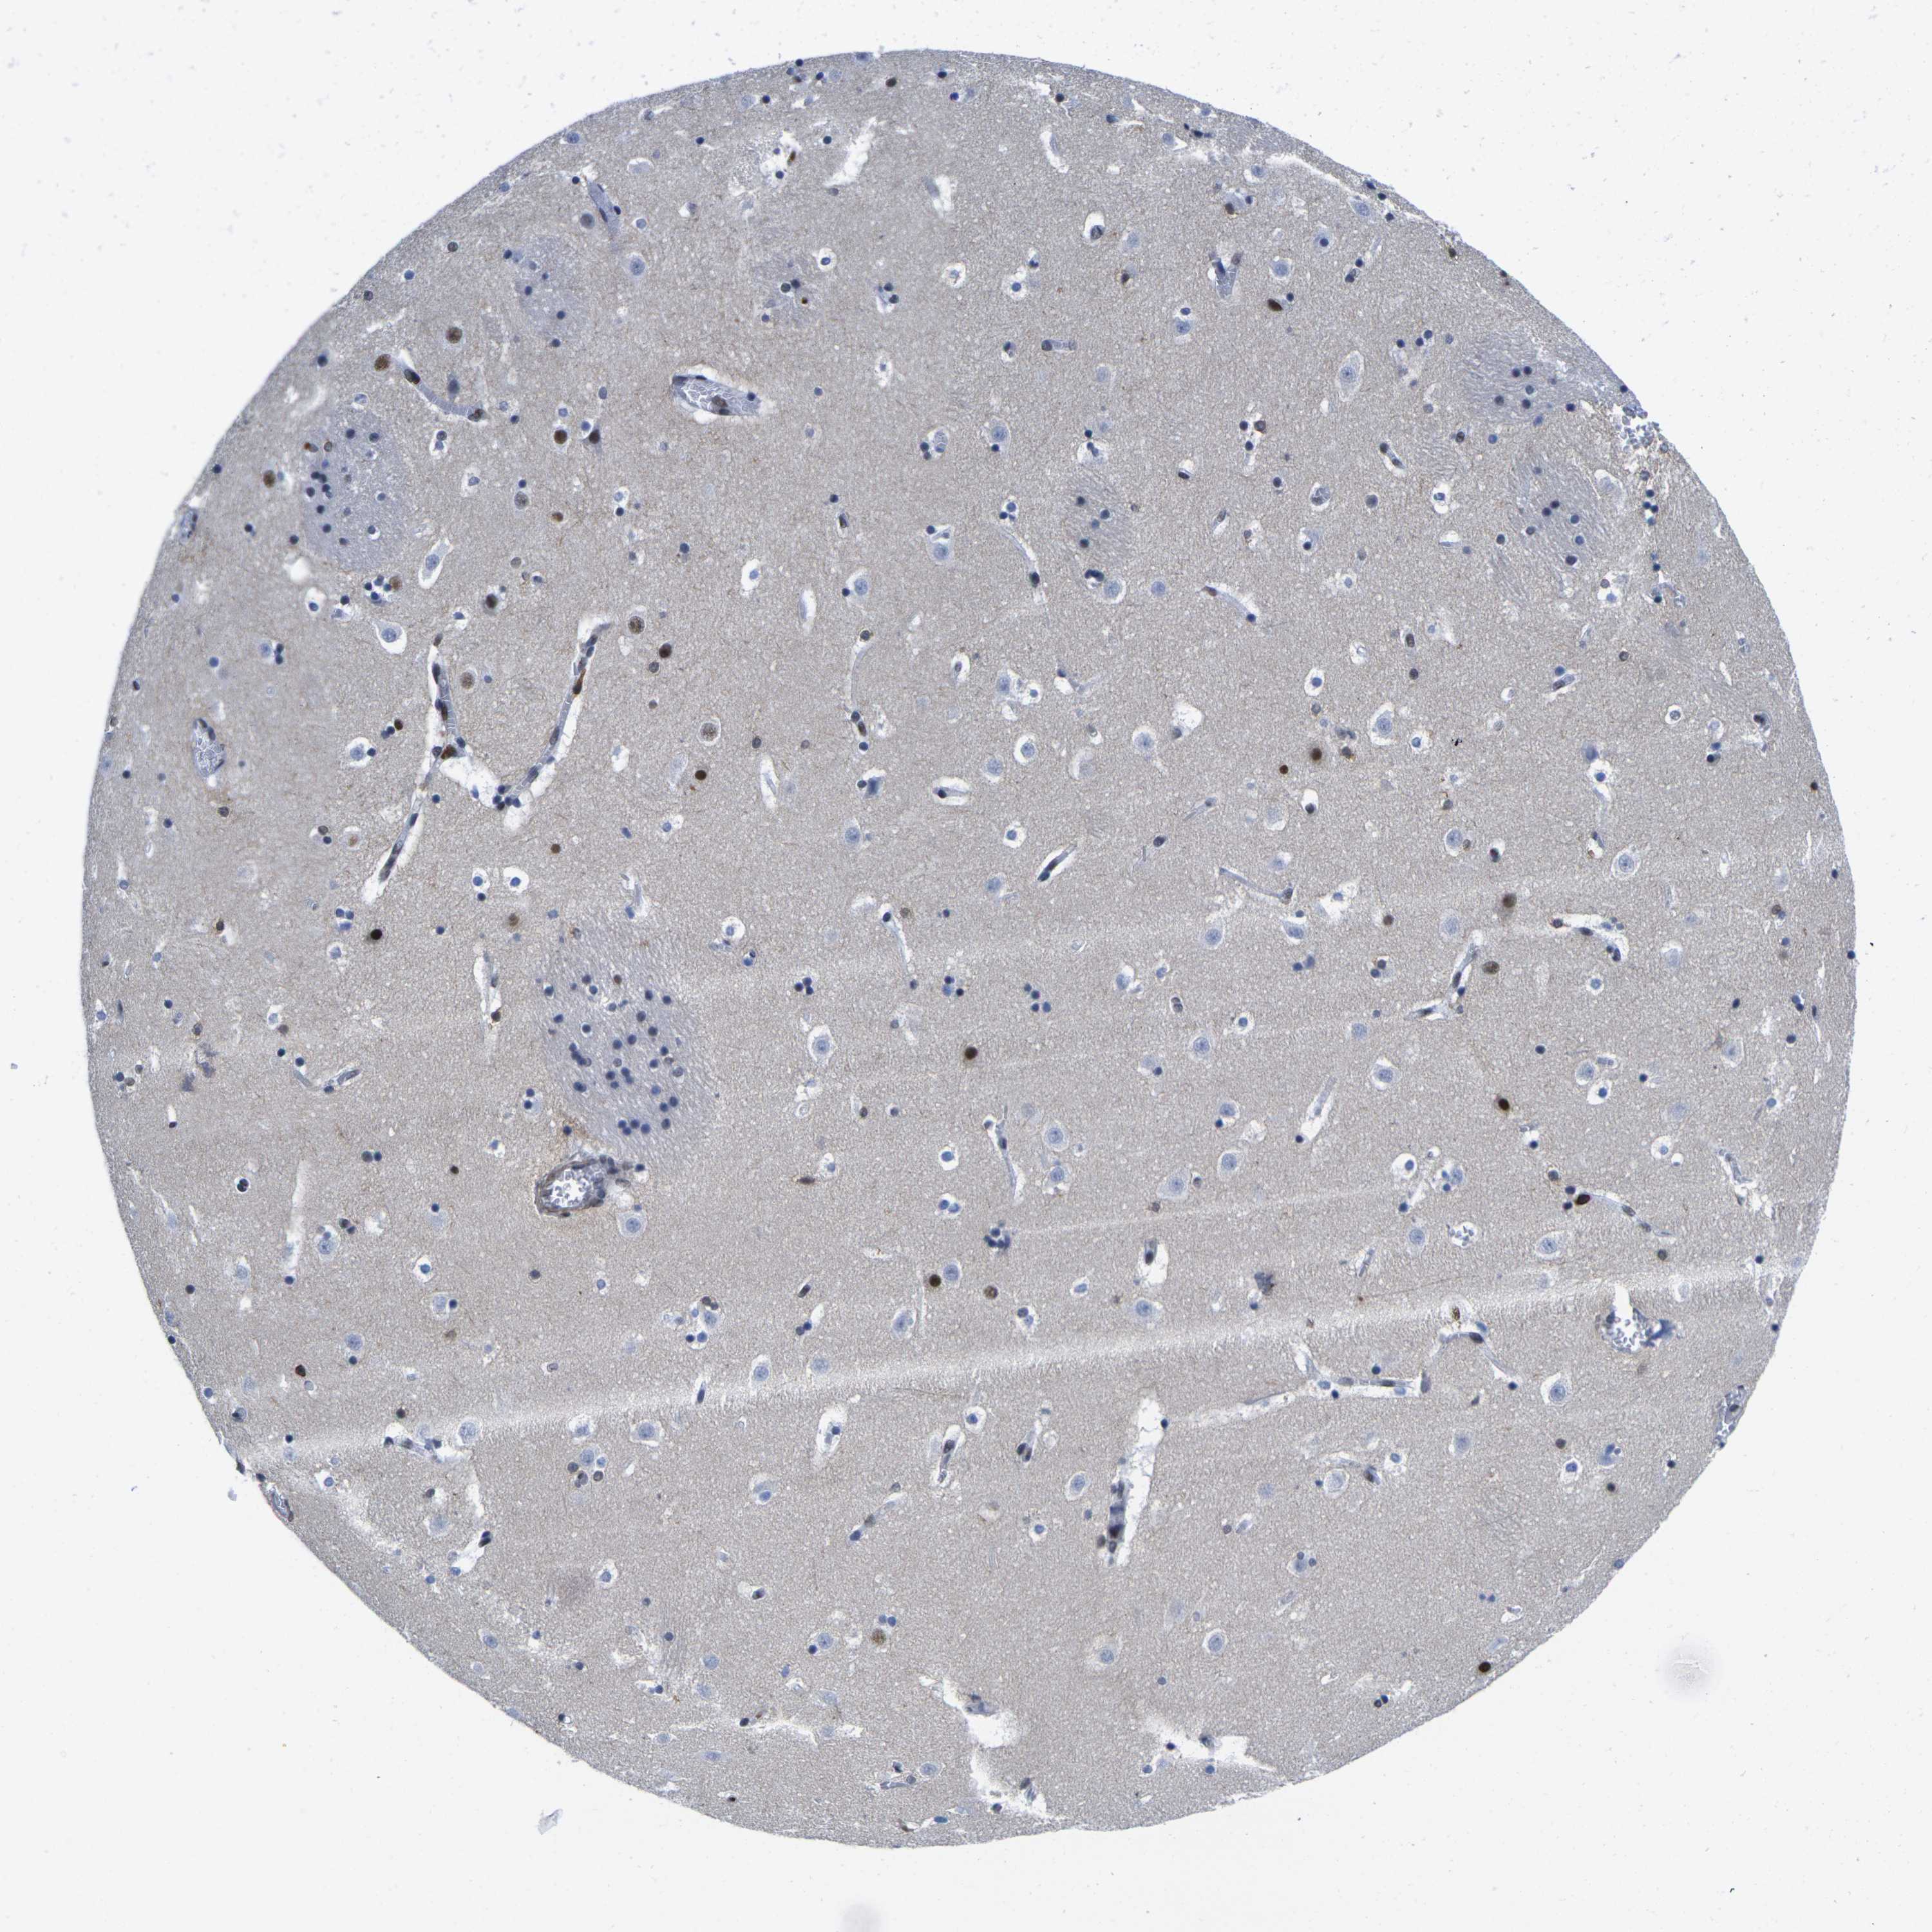

CAUDATE